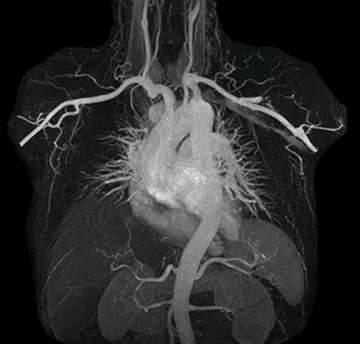

The subtractionless peripheral MR angiography shows improved vessel-to-background contrast and high resolution. Ingenia Ambition 1.5T.

Performed on Ingenia Ambition. FOV 430 mm, voxels 1.3 x 1.3 x3.0 mm, 130 slices, Breath hold 16.6 sec

Using mDIXON provides excellent fat saturation uniformity. No artifacts seen at the edges in these images, while these were quite commonly seen with eTHRIVE on our previous system. Note also the high resolution.

Ingenia Ambition, 3D breath hold, FOV 370 mm, voxels 1.51 x 1.58 x 4.0 mm, 120 slices, scan time 19.6 sec.